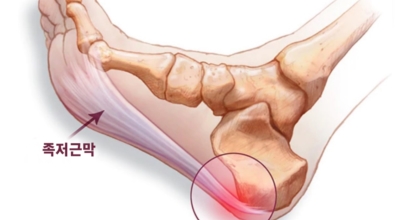

족저 근막이란 발가락 시작지점부터 발뒤꿈치뼈까지 발바닥 전체를 감싸고 있는 두꺼운 막을 말합니다. 족저 근막은 발바닥 아치를 지속시켜 발바닥이 지면을 내딛음으로써 발생하는 충격을 흡수하는 중요한 역할을 수행하고 있답니다. 이 족저 근막에 일차적으로 서서히 조직 손상이 일어나고 계속적인 활동으로 말미암아 염증이 커지면서 발 뒤꿈치 부근 통증을 일으키게 되는데 염증은 무리하고 반복적인 동작, 많은 사용으로 마찰에 의해 발생합니다.

족저 근막염은 염증에 의한 손상 및 통증을 유발하는 질환인데요 족저 근막염 증상은 일반적인 발뒤꿈치 통증 하글런드 병변의 기형으로 알려져 있으고 아킬레스 건과 관련이 깊다고 합니다. 특히 근육이 덜 풀린 아침 시간 대는 보행 시 날카롭고 바늘로 찌르는 듯한 심한 통증을 느끼게 된다고 합니다. 하지만 아침 시간 대를 지나 오후에 접어들면서 어느 정도 통증은 서서히 감소하기 시작한다고 하는데요 초기 증상이 나타난다면 꼭 전문의를 찾아 조기치료하는 것이 바람직합니다.